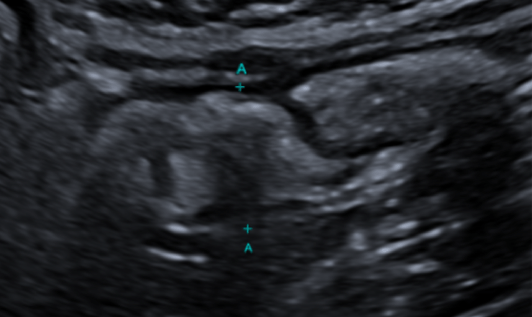

B-mode ultrasound and Contrast-enhanced ultrasound (CEUS)

An enlarged appendix is identified, measuring 15 mm in diameter and 4.8 cm in length, with a distal appendicolith measuring 8 mm (yellow arrow). After IV contrast administration, there is mural enhancement (2 mm) (Blue arrow) with no intraluminal contrast opacification. These findings suggest an appendiceal mucocele (mucinous neoplasm). No signs of complication are observed. (Fig. 1)